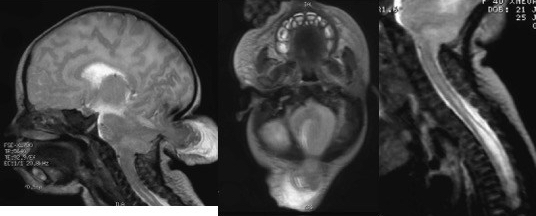

il s’agit d’une malformation extrêmement rare et de très mauvais pronostic, pouvant s’associer à des malformations multiples qui rendent l’enfant non viable.